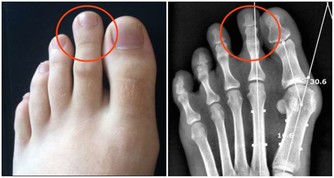

3.滑鼠手、晨僵往上翹

人們對手上的屈伸肌肉使用不平衡,經常使用屈肌,使伸肌功能退縮。

休息之餘你可以把雙手平放在桌子上,手掌不動,手指離開桌面上抬,反覆堅持1~2分鐘,會感覺手部肌肉舒服了很多。

長期使用電腦、有風濕關節痛、早上起來手指關節僵硬的朋友,可以用這個方法來鍛煉手關節,止痛。